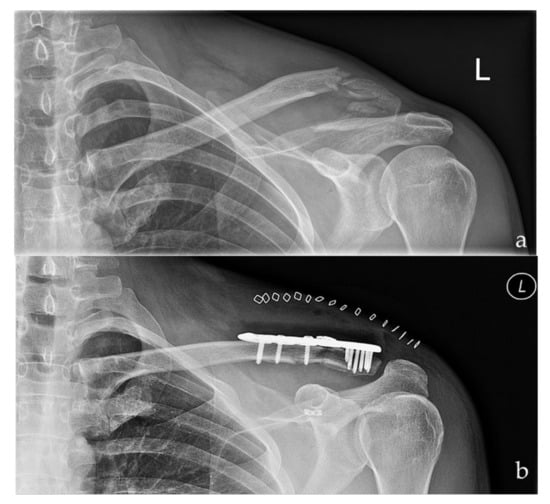

Figure 1. Preoperative (a) and postoperative (b) radiographs of a left sided multi-fragmentary, displaced lateral clavicle fracture (Neer IIb) after arthroscopic assisted fixation using a LCP and the knotted DogBone Technique (Group I).

The lateral clavicle fractures were addressed using a locking compression plate (Arthrex®, Naples, Florida, USA) and the coracoclavicular ligament injury was taken care of either by a knotted or knotless DogBone ™ (Arthrex, Naples, Florida, USA) Button technique, respectively (Figure 1 and Figure 2). A small longitudinal skin incision was carried out to address the lateral clavicle fracture. The fracture was reduced and stabilized using a locking compression plate. A routine diagnostic arthroscopic procedure followed by preparation of the coracoid base was performed. For preparation of the base of the coracoid process care has to be taken of the subscapularis tendon which lies below and directs medially to the coracoid process. Furthermore, the glenoid labrum should not be damaged during preparation. The musculocutaneous nerve must be taken care of as it lies medial to the coracoid base, why subtle preparation has to be performed in this region. The DogBone™ Button was inserted and either knotted (Group 1) or locked using a knotless (Group 2) technique. These two techniques have been compared to each other with respect to functional outcome and irritation rates.